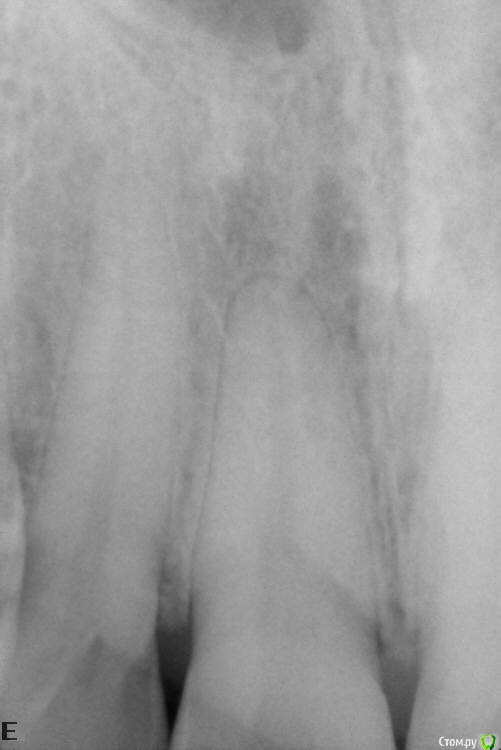

VladV Опубликовано 19 апреля, 2015 Поделиться Опубликовано 19 апреля, 2015 Помогите, пожалуйста, советом. Заранее извиняюсь за простыню. Около полутора месяцев назад пропустил два удара в голову. Один пришелся в верхнюю челюсть, другой в районе правой брови. Была сильно разбита верхняя губа, которая слиплась и срослась сама (не зашивали). Зубы, вроде бы, не беспокоили. Проверял холодом - реакция есть. Явных болевых ощущений не было, но как-то стал чувствовать верхнюю единицу (11), иногда совсем чуть-чуть зуб поднывал и было ощущение, что совсем немного сдвинулся назад, внутрь рта (возможно, всегда таким был, не обращал внимания). При смыкании зубов поверхностью верхнего к поверхности нижнего, а не нижний за верхний, явной боли не было, но я старался не смыкать лишний раз и не кусать этими зубами. Губа зажила где-то через две недели, только внутри уплотнение небольшое осталось. Не знаю, важно ли, но примерно после заживления губы то ли словил вирус, то ли есть связь с зубами, но начался сильный насморк, который длился недели две и вторая неделя была с густыми зелеными (простите за подробности) выделениями и даже иногда кровь шла из носа от попыток их вымыть и высморкать.Спустя месяц, когда насморк прошел, решил сходить к стоматологу в частную клинику и проверить зубы на всякий случай, т.к. непонятные ощущения в 11 зубе остались. Простучали зубы 22-21-11-12. У всех зубов чувствительность одинаковая, у 11 чуть сильнее. Сделали несколько прицельных снимков. Врач ничего криминального с корнями не обнаружил. Посоветовали сделать чистку зубов ультразвуком и AirFlow, т.к. был сильный налет и отложение камня.Через пару дней сделал чистку. Полтора часа чистили все зубы, так как около 5 лет до этого не чистил. Врач долго не мог понять, что за смолянистый темный налет был на зубах (не курю и кофем не злоупотребляю), в итоге выяснили, что из-за постоянного полоскания ротовыми ополаскивателями, содержащими хлор. Увлекался ими последние полгода. После травмы зуба казалось, что после ополаскивания зубу легче становилось и его долго ничего не беспокоило. Во время осмотра между верхними единицами обнаружился легкий кариес. Врач сказал, что на корни и мои ощущения 11 зуба он никак влиять не может. После чистки местами были травмированы десны, местами маленькие гематомы были, некоторые зубы стали особенно чувствительно переносить холодное и горячее. Но то ли так совпало, то ли из-за чистки, 11 зуб стал чаще поднывать, причем, непонятные ощущения переместились ближе к пространству между 11 и 12 зубом, и на 12 зуб вроде бы тоже стали распространяться. Сложно описать, но такое ощущение, что чувствительность куда-то ближе к носу ушла, иногда как будто напряжение какое-то между зубами возникало, будто еда застряла. Стал непроизвольно тсыкать - прислонять язык к щели 11-12, 11-21, 12-13 и втягивать резко воздух, так легче что ли становилось или из-за ощущений от увеличенных просветов между зубами. Потом то ли из-за того, что не пользуюсь передними зубами, то ли из-за чего-то другого, но появилось ощущение, что изменился прикус. Нижние единицы стали как-то ощутимее упираться в верхние единицы, будто в другом месте из-за якобы ушедшей чуть-чуть вперед нижней челюсти. Иногда верхние единицы становились как чужие, снижалась чувствительность что ли. Иногда кажется соленоватый привкус у десны между 11 и 12 зубами, хотя крови и каких-либо выделений в слюне нет. В какие-то дни эти ощущения уходили, в какие-то возвращались. Заметил, что у 11 зуба есть небольшая подвижность, определил прислоняя палец к щели 11-12 и сжимая/расслабляя челюсти. Понаблюдав неделю пошел уже в другую частную клинику. Там опять сделали снимки (прилагаю к сообщению), опять ничего криминального не обнаружили. Кариес легкий между 11 и 21 видят, рекомендуют убрать и отреставрировать зубы, но не видят связи с моими ощущениями. Сказали, наблюдать дальше за зубом, сделать контрольные снимки месяца через три и не заморачиваться. Легко им говорить, у меня уже паранойя развиваться начала. Каждое утро просыпаюсь и сразу прислушиваюсь к ощущениям, потом весь день то отвлекаешься, то опять вспоминаешь и тсыкаешь. Все еще осложняется тем, что в двадцатых числах я почти на 20 дней улетаю в Египет, где если и случится чего, то вряд ли смогут квалифицированно помочь с зубами.В итоге решил поискать информацию в Интернете и наткнулся на этот форум. Начитался ужасов всяких и еще больше теперь боюсь уезжать. Правда, непонятные ощущения после этого стали реже возвращаться, уже пару дней, испугались, наверно. Записался на панорамный снимок, который и прикладываю. Прошу специалистов высказать свое мнение. Действительно ли забить и жить с этими непонятными ощущениями или дальше копать. Какие препараты лучше взять на случай, если что-то пойдет не так в поездке? Заранее спасибо за рекомендации и еще раз простите за простыню. Ссылка на комментарий